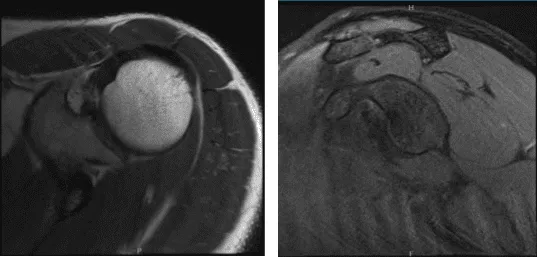

Tras tres meses, el paciente volvió a la consulta aún quejándose de dolor bilateral en el hombro. Aconsejé al paciente que se sometiera a una resonancia magnética para ver alguna mejoría respecto a la última visita. La resonancia magnética del hombro derecho seguía mostrando esguince crónico de la articulación AC.

Resonancia – 3T hombro derecho sin contraste